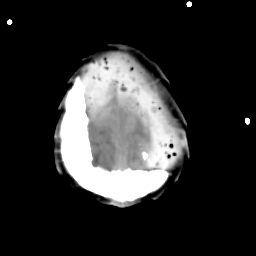

Meningioma: Roentgen-ray CT #2 -- Slice #20

[Home][Help][Clinical] Slice 20